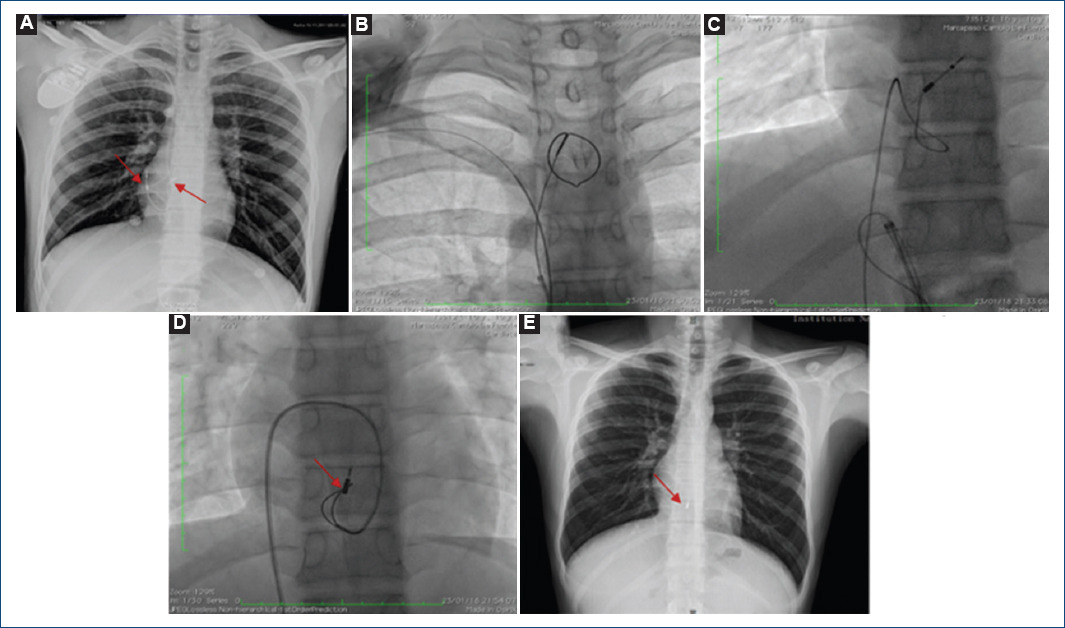

Adolescente de 16 años de edad (fecha de nacimiento: 11/01/2002), producto de la primera gestación, de embarazo normoevolutivo, obtenido de término a las 38 semanas de gestación por vía vaginal, con puntuación de Apgar 9/9, eutrófico, con neurodesarrollo normal. Madre y tío materno con síndrome de QT largo (SQTL), resto de familiares aparentemente sanos. El niño fue diagnosticado con SQTL tipo 2 a los nueve años de edad (en 2011). Recibió tratamiento betabloqueador (propranolol 1 mg/kg/día) con adecuada respuesta, pero requirió del implante de un marcapasos definitivo bicameral el 14 de noviembre de 2017 por disfunción sinusal (bradicardia sintomática). Casi dos meses después tuvo que ser hospitalizado por exteriorización de electrodo de marcapaso e infección del sistema. Se realizó retirada del sistema el 23 de enero del 2018, requiriendo abordaje tanto por vía pectoral como femoral derecha y quedando la punta del electrodo ventricular en el septum interventricular. Se envió a cultivo tanto el material extraído como una muestra de secreción de la herida y se realizaron hemocultivos. En estos últimos se aisló Staphylococcus aureus, por lo que recibió tratamiento para endocarditis por 45 días. Para intentar preservar los accesos vasculares, se valoró para implante de DAI-SC. Se realizó el escrutinio preimplante, el cual fue positivo, por lo que fue llevado a implante del equipo de DAI-SC (Emblem, Boston Scientific, EE.UU.) en el Laboratorio de Electrofisiología el día 23 de marzo de 2018. En la radiografía de tórax previa al alta se comprobó la normoposición del electrodo y el generador (Fig. 2). Se egresó el 26 de marzo y se mantuvo asintomático hasta el 31 de mayo, dos meses después del implante, cuando presentó dos eventos de FV postesfuerzo (jugando a fútbol), ambos a una frecuencia mayor de 220 lpm y que fueron terminados adecuadamente por el equipo con descargas de 41 Joules. Este caso constituye el primer caso de un implante de DAI-SC en un paciente pediátrico en Latinoamérica (Fig. 3).

Figura 2 Caso 2. Paciente con síndrome de QT Largo. A: radiografía de tórax donse se observan marcpasos bicameral con generador derecho, cable auricular y ventricular bien implantados. B, C y D: imágenes fluoroscópicas que muestran el retiro de los cables. E: la flecha señala la punta remanente del electrodo ventricular.